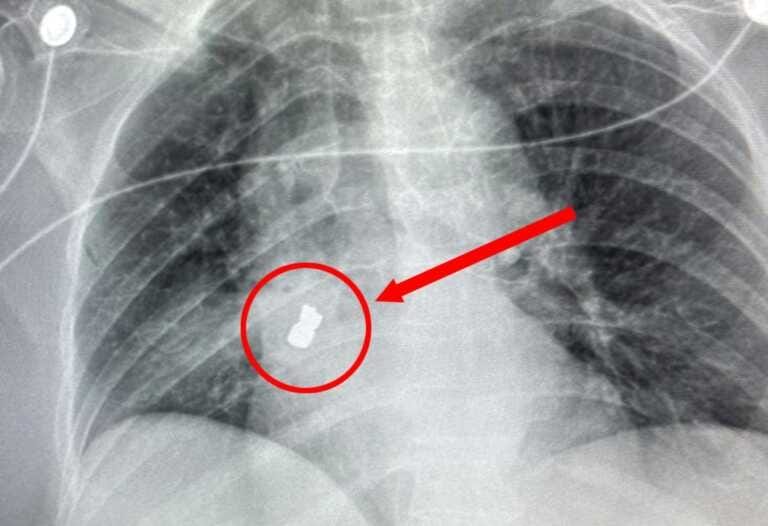

Una radiografia ha rivelato la presenza del corpo estraneo nelle vie aeree ed un addensamento con una polmonite circostante.

«Si è palesata la possibilità che la signora – ha spiegato Cristiano Carbonelli, medico responsabile dell’Unità di pneumologia interventistica dell’Irccs ‒ avesse inalato un piccolo pezzo di protesi dentaria. A questa ipotesi – ha aggiunto – corrispondeva la forma del corpo estraneo evidenziato dalla radiografia: due cuspidi dentali unite da un ponte sottostante che si localizzava nel polmone».